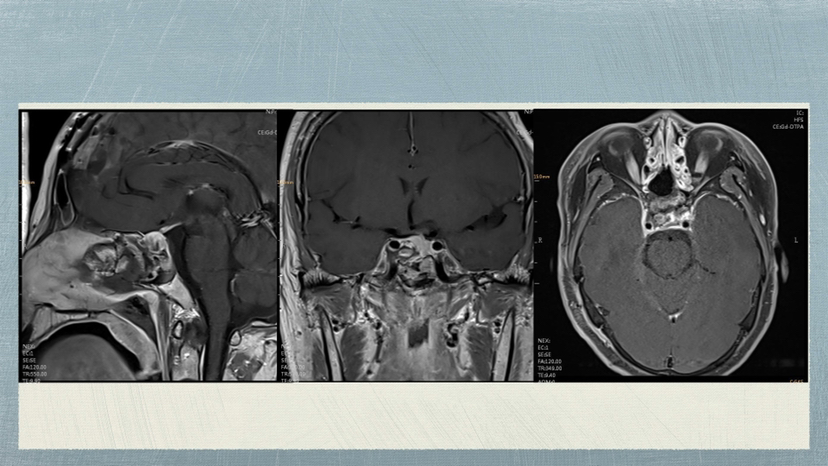

“侵袭性垂体腺瘤合并大脑镰脑膜瘤”病例 (神经内镜下切除垂体瘤,显微镜下切除脑膜瘤)

脑肿瘤-脑膜瘤

脑肿瘤-垂体瘤

脑膜瘤

垂体瘤

垂体腺瘤